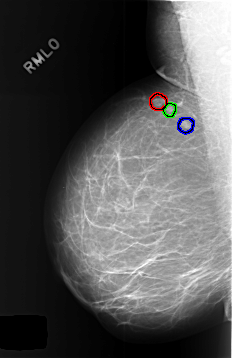

C_0446_1.RIGHT_MLO

LEFT_MLO LINES 5680 PIXELS_PER_LINE 3992 BITS_PER_PIXEL 12 RESOLUTION 50 NON_OVERLAY

FILE: C_0446_1.RIGHT_MLO.OVERLAY

TOTAL_ABNORMALITIES 3

ABNORMALITY 1

LESION_TYPE MASS SHAPE LOBULATED MARGINS CIRCUMSCRIBED

ASSESSMENT 3

SUBTLETY 5

PATHOLOGY BENIGN_WITHOUT_CALLBACK

ABNORMALITY 2

LESION_TYPE MASS SHAPE ROUND MARGINS CIRCUMSCRIBED

ABNORMALITY 3

LESION_TYPE MASS SHAPE OVAL MARGINS CIRCUMSCRIBED